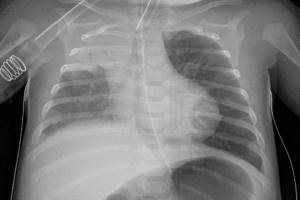

Негоспітальна пневмонія

Під негоспітальною пневмонією (НП) слід розуміти гостре захворювання, що виникло в позалікарняних умовах та супроводжується симптомами інфекції нижніх дихальних шляхів (лихоманка; кашель; виділення харкотиння, можливо гнійного; біль у грудях та задишка) і рентгенологічними ознаками нових вогнищево-інфільтративних змін у легенях за відсутності очевидної діагностичної альтернативи.

Діагноз НП є визначеним за наявності у хворого рентгенологічно підтвердженої вогнищевої інфільтрації легеневої тканини та не менше 2 клінічних ознак із нижченаведених:

Нозокоміальна (госпітальна) пневмонія (ГП) – захворювання, що характеризується появою на рентгенограмі нових вогнищево-інфільтративних змін у легенях через 48 год і більше після госпіталізації в поєднанні з клінічною симптоматикою, яка підтверджує їхню інфекційну природу (нова хвиля лихоманки, гнійне харкотиння або гнійне виділення із трахеобронхіального дерева, лейкоцитоз та ін.), при виключенні інфекцій, що знаходилися в інкубаційному періоді на момент надходження хворого до стаціонару.

Незважаючи на відомі обмеження, клінічне обстеження залишається «відправною точкою» діагностики ГП, а дані інших методів (у тому числі й інвазивних) лише інтерпретують з урахуванням клінічної картини ГП. Для ГП характерна поява нових інфільтративних змін на рентгенограмі органів грудної клітки в поєднанні з такими ознаками інфекційного захворювання, як лихоманка, виділення гнійного харкотиння і/або лейкоцитоз. У зв’язку з цим до формалізованих діагностичних критеріїв ГП відносять:

1. появу на рентгенограмі нових вогнищево-інфільтративних змін у легенях;

2. дві з наведених нижче ознак: